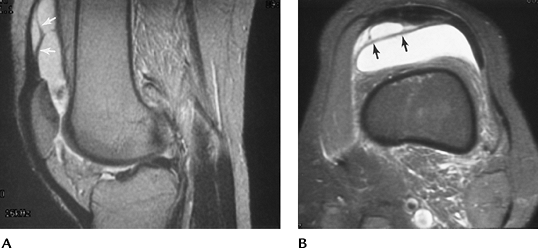

![]() |

FIGURE 5-50 Normal radiographic relationships. (A) Sulcus angle formed by lines along the femoral condyles is normally 138 to 142 degrees. (B)

Lateral radiograph with the knee flexed 30 degrees. The patellar tendon (PT) length over the patellar height (PH) = 1.02 ± 0.13. (C) The medial patellar edge should be at or just medial to a line (M) perpendicular to a line (C) along the condylar margins. |